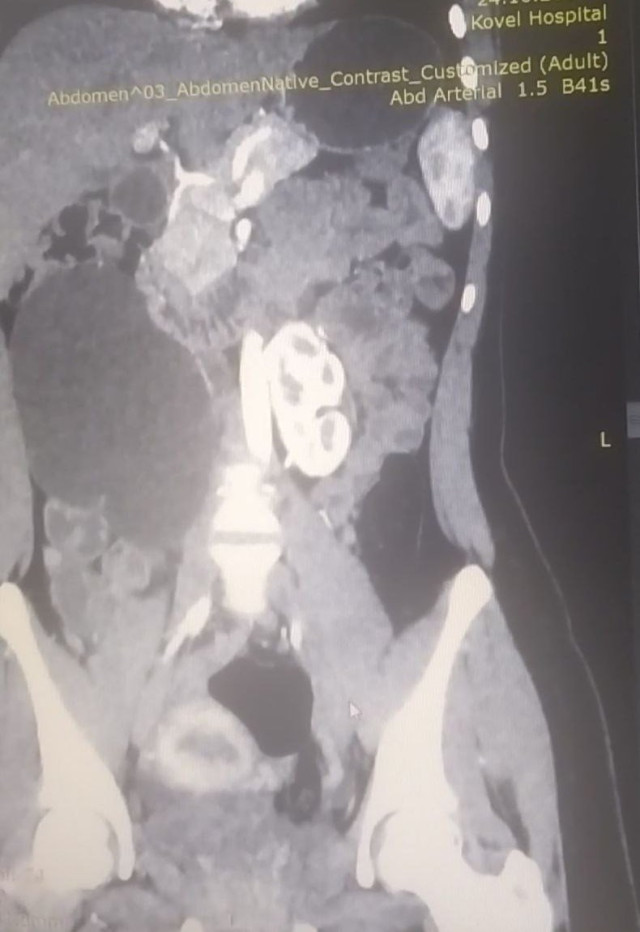

Вперше у Ковелі провели унікальну урологічну операцію 17-річній пацієнтці, яка мала вроджену ваду сечовидільної системи – підковоподібну нирку (зрощення двох нирок). Стан її здоров’я погіршувався упродовж багатьох років, аж поки права половина підковоподібної нирки перестала функціонувати.

Хвору доставили в лікарню у важкому стані з вираженим больовим синдромом та наявністю гіпертонічного кризу. Через звуження у сечоводі та ускладнення відтоку сечі, об’єм рідини в нирці сягнув критичного рівня. А збільшення її розмірів стало помітним навіть зовні.

Лікарі діагностували термінальний гідронефроз із наслідками, гідронефротичну трансформацію правої половини підковоподібної нирки, вторинну артеріальну гіпертензію.

Команда фахівців - Остап Звоздяк, Микола Дем’янчук, Олег Кубай - успішно виконала лапароскопічну гемінефруретеректомію правої половини підковоподібної нирки (мінілапаротомія за Пфанненштилем з видаленням макропрепарата). Дренування черевної порожнини.